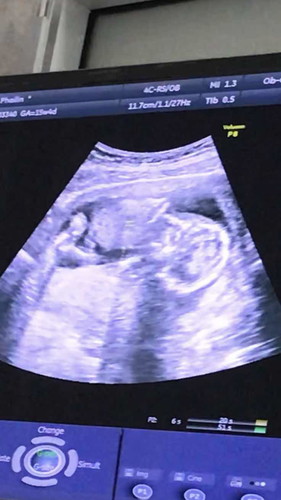

ไปซาวดูเพศ 2 รอบแล้ว รอบแรกหลับ นอนนิ่งเลยคะ พอรอบ 2 พึ่งไปมาเมื่อวาน นอนหันหลังให้เลย55555 #อยากรู้เพศใจจะขาดแล้ว? #เจ้าดื้อ? #มีเด็กบ้านใครดื้อเหมือนเด็กเรามั้ย5555555?

ของเราก้อเป็นค่ะ รอบแรกนอนคว่ำเขย่าก้อไม่ขยับหมอบอกน่าจะหลับ พอรอบสองไปนอนหงายแต่หนีขาหมอซาวด์ให้ดูหน้าเหนแค่ครึ่งหน้า ไม่รุ้เพศสักที่รอเหมือนกันค่ะอยากดูเพศลูก ว่าได้ลูกสาว หรือลูกชาย😁😁

อ่านเพิ่มเติมเหมือนกันเลยค่ะบ้านนี้ไปรอบแรกหันก้นให้ดูไปรอบสองคว่ำไม่ให้เห็นพรุ่งนี้หมอนัดไม่รุ้จะได้เห็นเพศรึป่าวแม่บ้านนี้เตรียมของไม่ถูกเลยจ้าา